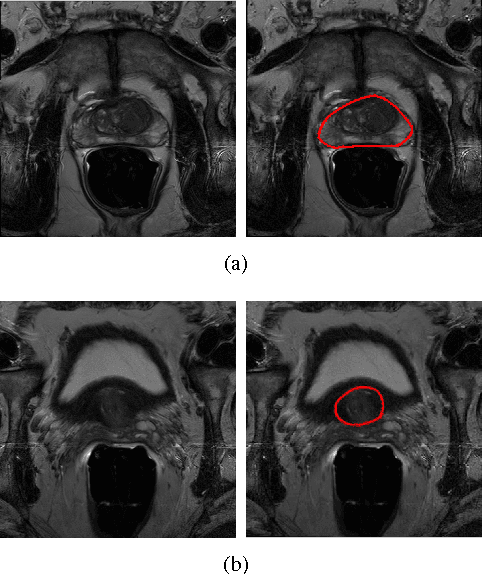

Abstract:Accurate segmentation of the prostate from magnetic resonance (MR) images provides useful information for prostate cancer diagnosis and treatment. However, automated prostate segmentation from 3D MR images still faces several challenges. For instance, a lack of clear edge between the prostate and other anatomical structures makes it challenging to accurately extract the boundaries. The complex background texture and large variation in size, shape and intensity distribution of the prostate itself make segmentation even further complicated. With deep learning, especially convolutional neural networks (CNNs), emerging as commonly used methods for medical image segmentation, the difficulty in obtaining large number of annotated medical images for training CNNs has become much more pronounced that ever before. Since large-scale dataset is one of the critical components for the success of deep learning, lack of sufficient training data makes it difficult to fully train complex CNNs. To tackle the above challenges, in this paper, we propose a boundary-weighted domain adaptive neural network (BOWDA-Net). To make the network more sensitive to the boundaries during segmentation, a boundary-weighted segmentation loss (BWL) is proposed. Furthermore, an advanced boundary-weighted transfer leaning approach is introduced to address the problem of small medical imaging datasets. We evaluate our proposed model on the publicly available MICCAI 2012 Prostate MR Image Segmentation (PROMISE12) challenge dataset. Our experimental results demonstrate that the proposed model is more sensitive to boundary information and outperformed other state-of-the-art methods.

Abstract:Prostate segmentation from Magnetic Resonance (MR) images plays an important role in image guided interven- tion. However, the lack of clear boundary specifically at the apex and base, and huge variation of shape and texture between the images from different patients make the task very challenging. To overcome these problems, in this paper, we propose a deeply supervised convolutional neural network (CNN) utilizing the convolutional information to accurately segment the prostate from MR images. The proposed model can effectively detect the prostate region with additional deeply supervised layers compared with other approaches. Since some information will be abandoned after convolution, it is necessary to pass the features extracted from early stages to later stages. The experimental results show that significant segmentation accuracy improvement has been achieved by our proposed method compared to other reported approaches.